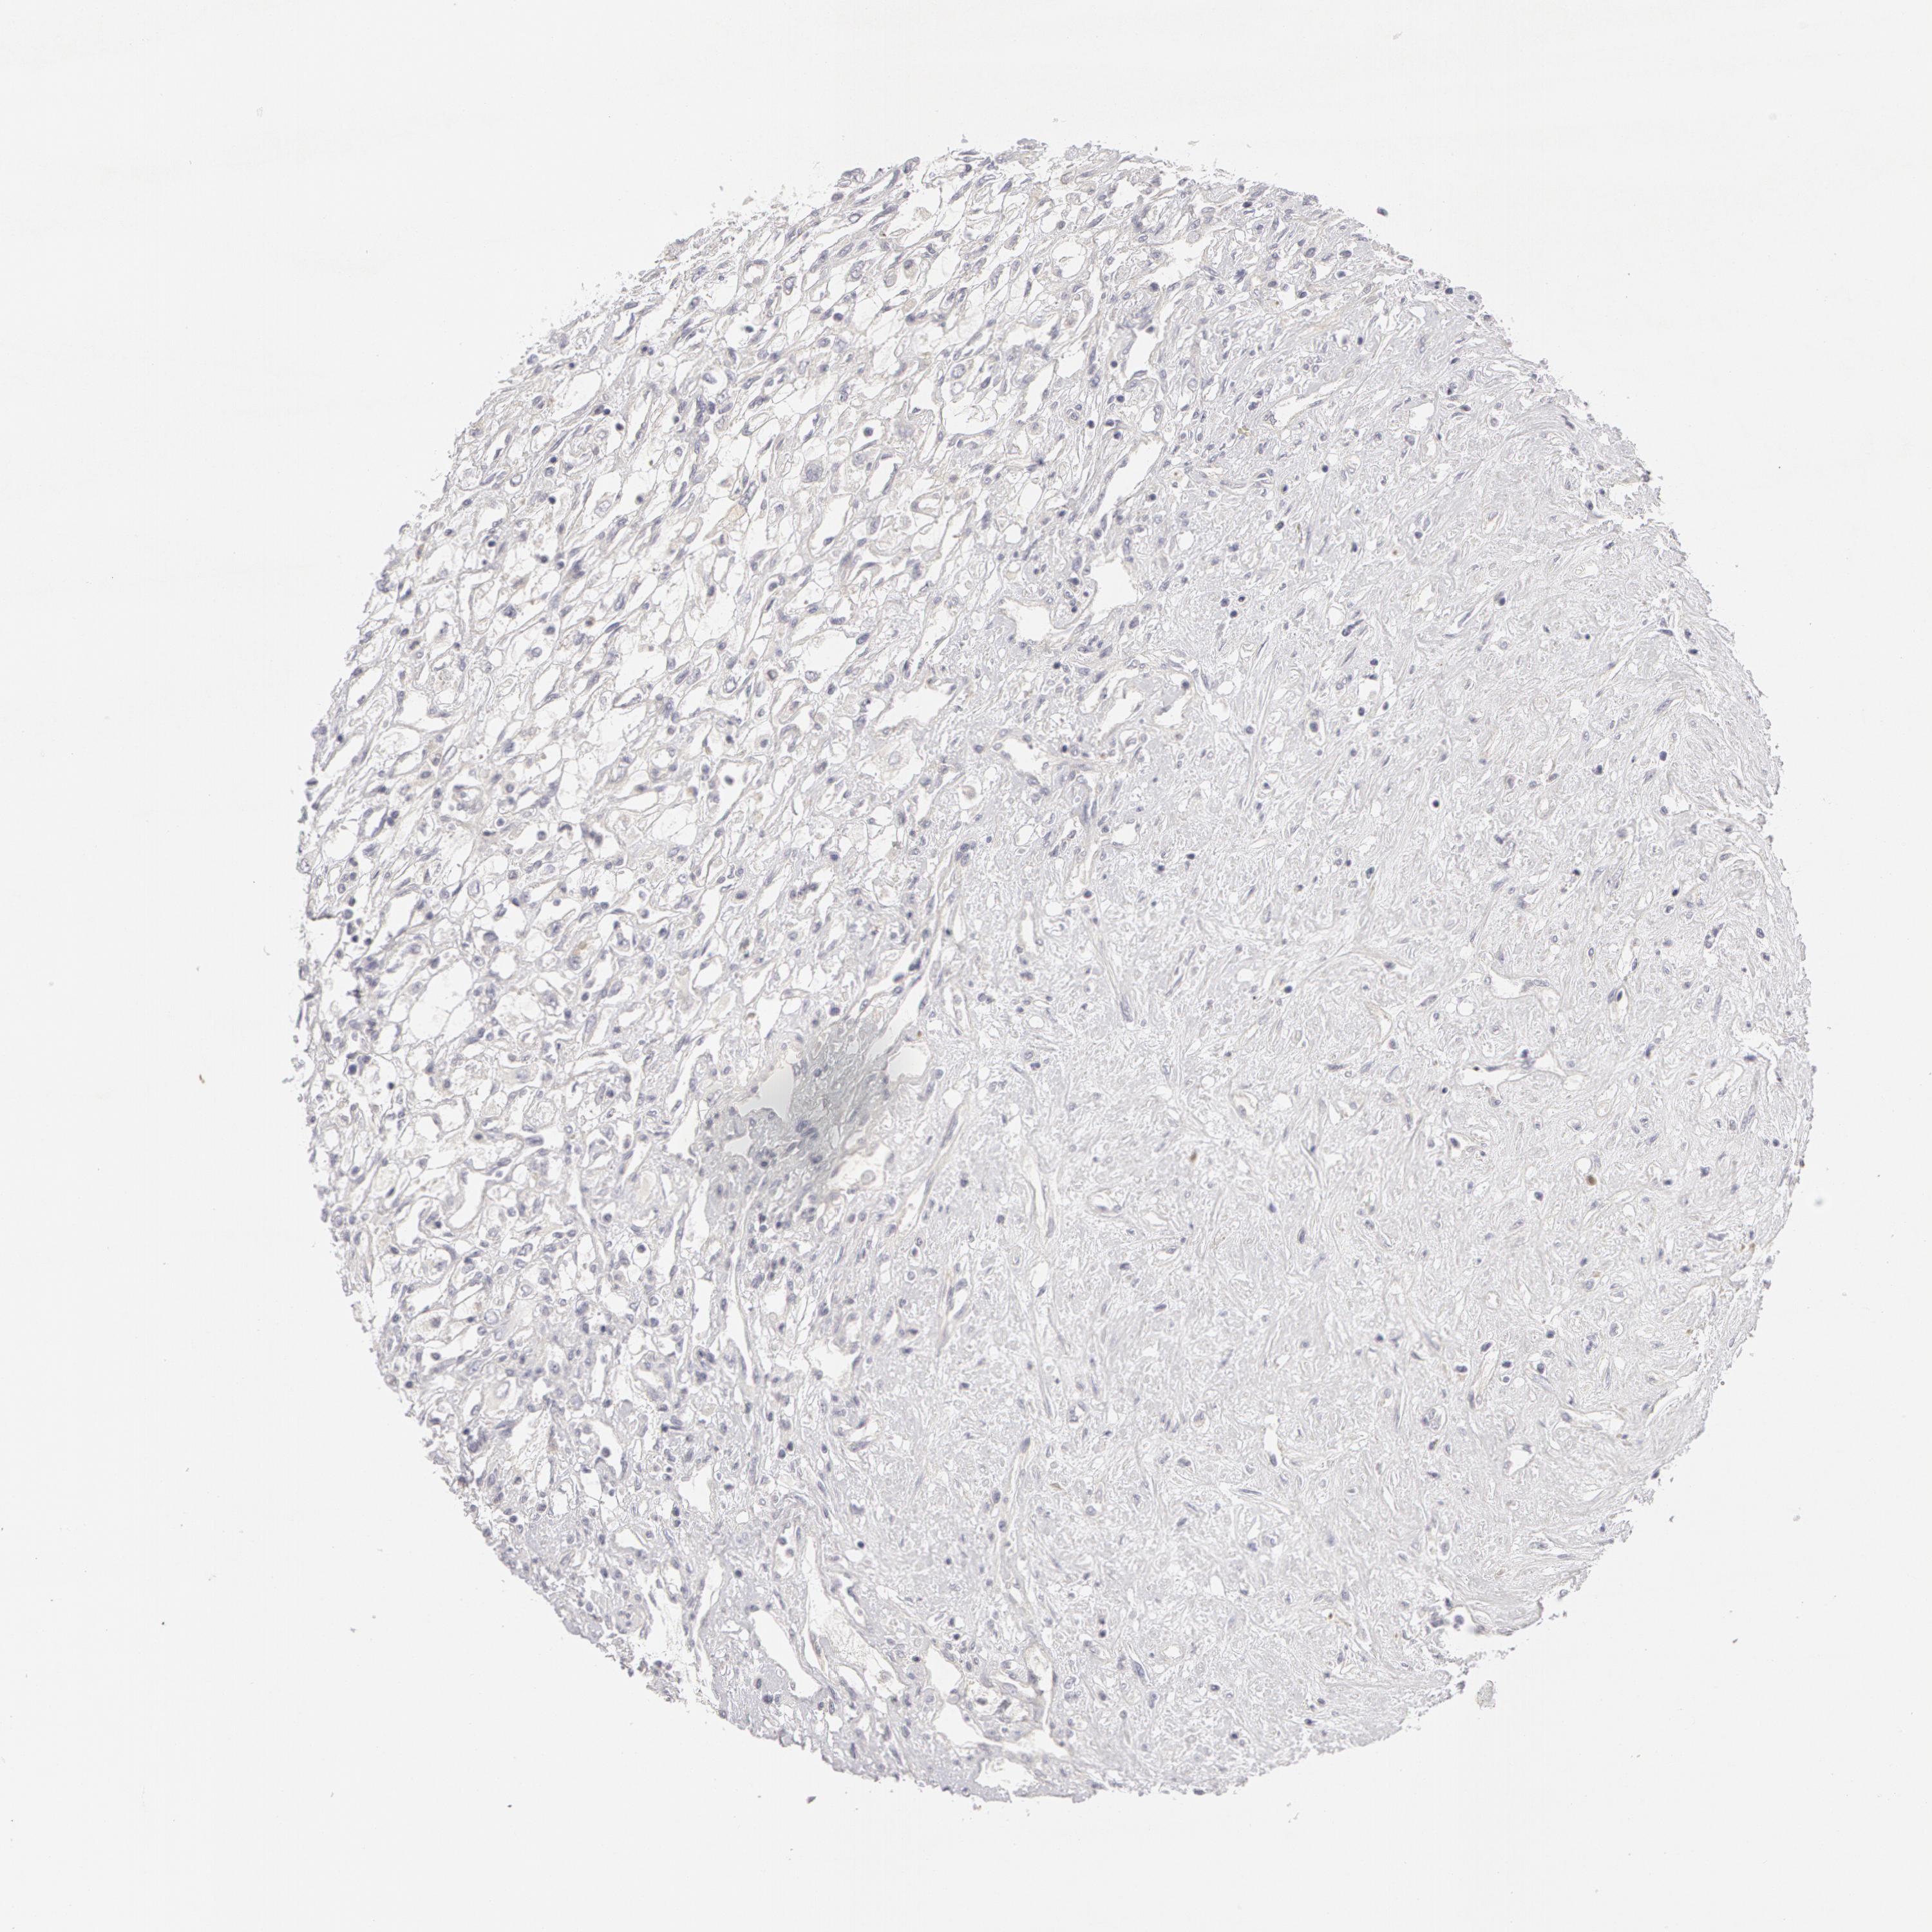

KIDNEY RENAL CLEAR CELL CARCINOMA (VALIDATION) - Interactive survival scatter ploti

The Survival Scatter plot shows the clinical status (i.e. dead or alive) for all individuals in the patient cohort, based on the same data that underlies the corresponding Kaplan-Meier plots. Patients that are alive at last time for follow-up are shown in blue and patients who have died during the study are shown in red.

The x-axis shows the expression levels (FPKM) of the investigated gene in the tumor tissue at the time of diagnosis. The y-axis shows the follow-up time after diagnosis (years). Both axes are complimented with kernel density curves demonstrating the data density over the axes. The top density plot shows the expression levels (FPKM) distribution among dead (red) and alive patients (blue). The right density plot shows the data density of the survived years of dead patients with high and low expression levels respectively, stratified using the cutoff indicated by the vertical dashed line through the Survival Scatter plot. This cutoff is automatically defined based on the FPKM cutoff that minimizes the p-score. The cutoff can be changed by dragging the vertical line or by entering a cutoff value in the square labeled "Current cut-off".

Under the Survival Scatter plot the p-score landscape (black curve; left axis) is shown together with dead median separation (red curve; right axis). Dead median separation is the difference in median mRNA expression between patients who have died with high and low expression, respectively. It is calculated as follows: median FPKM expression of dead patients with high expression - median FPKM expression of dead patients with low expression. This is intended to aid the user in visually exploring custom cutoffs and the associated p-scores and dead median separation.

Individual patient data is displayed and can be filtered by clicking on one or more of the category buttons on the top of the page. Categories describing expression level and patient information include: high, low, alive, dead, female, male and tumor stages. The scale of the x-axis can be toggled between linear and log-scale by clicking on the "x log" button. Mouse-over function shows TCGA ID, patient information and mRNA expression (FPKM) for each patient.

& Survival analysisi

Kaplan-Meier plots summarize results from analysis of correlation between mRNA expression level and patient survival. Patients were divided based on level of expression into one of the two groups "low" (under cut off) or "high" (over cut off). X-axis shows time for survival (years) and y-axis shows the probability of survival, where 1.0 corresponds to 100 percent.

ABCB1 is not prognostic in Kidney Renal Clear Cell Carcinoma (validation)

: 4.35

Average pTPM 22.5

Number of samples 100